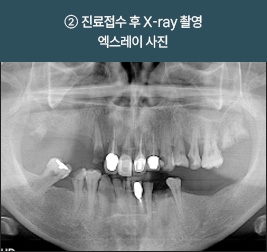

전북 외곽 지역에서 먼 걸음 해주신 환자분입니다

치아 손실로 오랜 기간 불편함을 겪으셨고, 잇몸뼈 흡수가 진행된 상태였습니다.

정밀 진단을 통해 잔존 치조골을 평가하고, 풀아치 임플란트 계획을 세워 단계적으로 치료를 진행했습니다.

I      올온포 풀아치 임플란트 사례      I

치료 기간 : 2021.03.12 ~ 2021.08.25

치료 기간 : 2021.06.05 ~ 2021.12.10